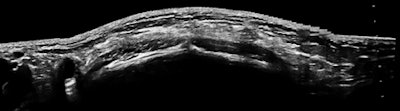

![]()  |

| Ultrasound image and photo of 19-year-old runner with localized lower right quadrant pain. |

The only trick here is to begin the exam with the patient upright after walking. I won't say much about inguinal hernias, except that they occur in perhaps 2% of children, more often in boys (not her, obviously), more often with premature birth (didn't ask), and there is a familial pattern (which there was). I thought it might be fair to match a big field-of-view image with the magnified small field of the first case. When you are providing images to referring physicians, who are not imaging experts, let the image fit the pathology, or should that be punishment and crime?